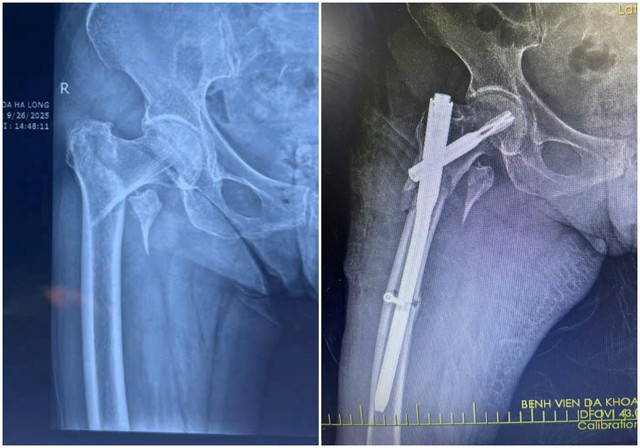

Kết quả chụp X-quang xác định bệnh nhân bị gãy liên mấu chuyển xương đùi. Với tình trạng tuổi cao, sức yếu, việc vận chuyển bệnh nhân hạn chế, tiềm ẩn nguy cơ làm vị trí gãy thêm trầm trọng.

Qua đường rạch da nhỏ khoảng 3-5cm, phẫu thuật viên nắn chỉnh xương gãy về vị trí giải phẫu, sau đó cố định bằng đinh nội tủy PFNA dưới màn hình tăng sáng (C-arm).

Phẫu thuật kết hợp xương ít xâm lấn với đường rạch da chỉ khoảng 3 - 5cm, cho phép nắn chỉnh và cố định vững chắc xương gãy bằng đinh nội tủy dưới sự hỗ trợ của màn hình tăng sáng C-arm. Kỹ thuật này giúp hạn chế tổn thương cơ, mạch máu và mô lành xung quanh, giảm nguy cơ nhiễm trùng, biến chứng sau mổ.